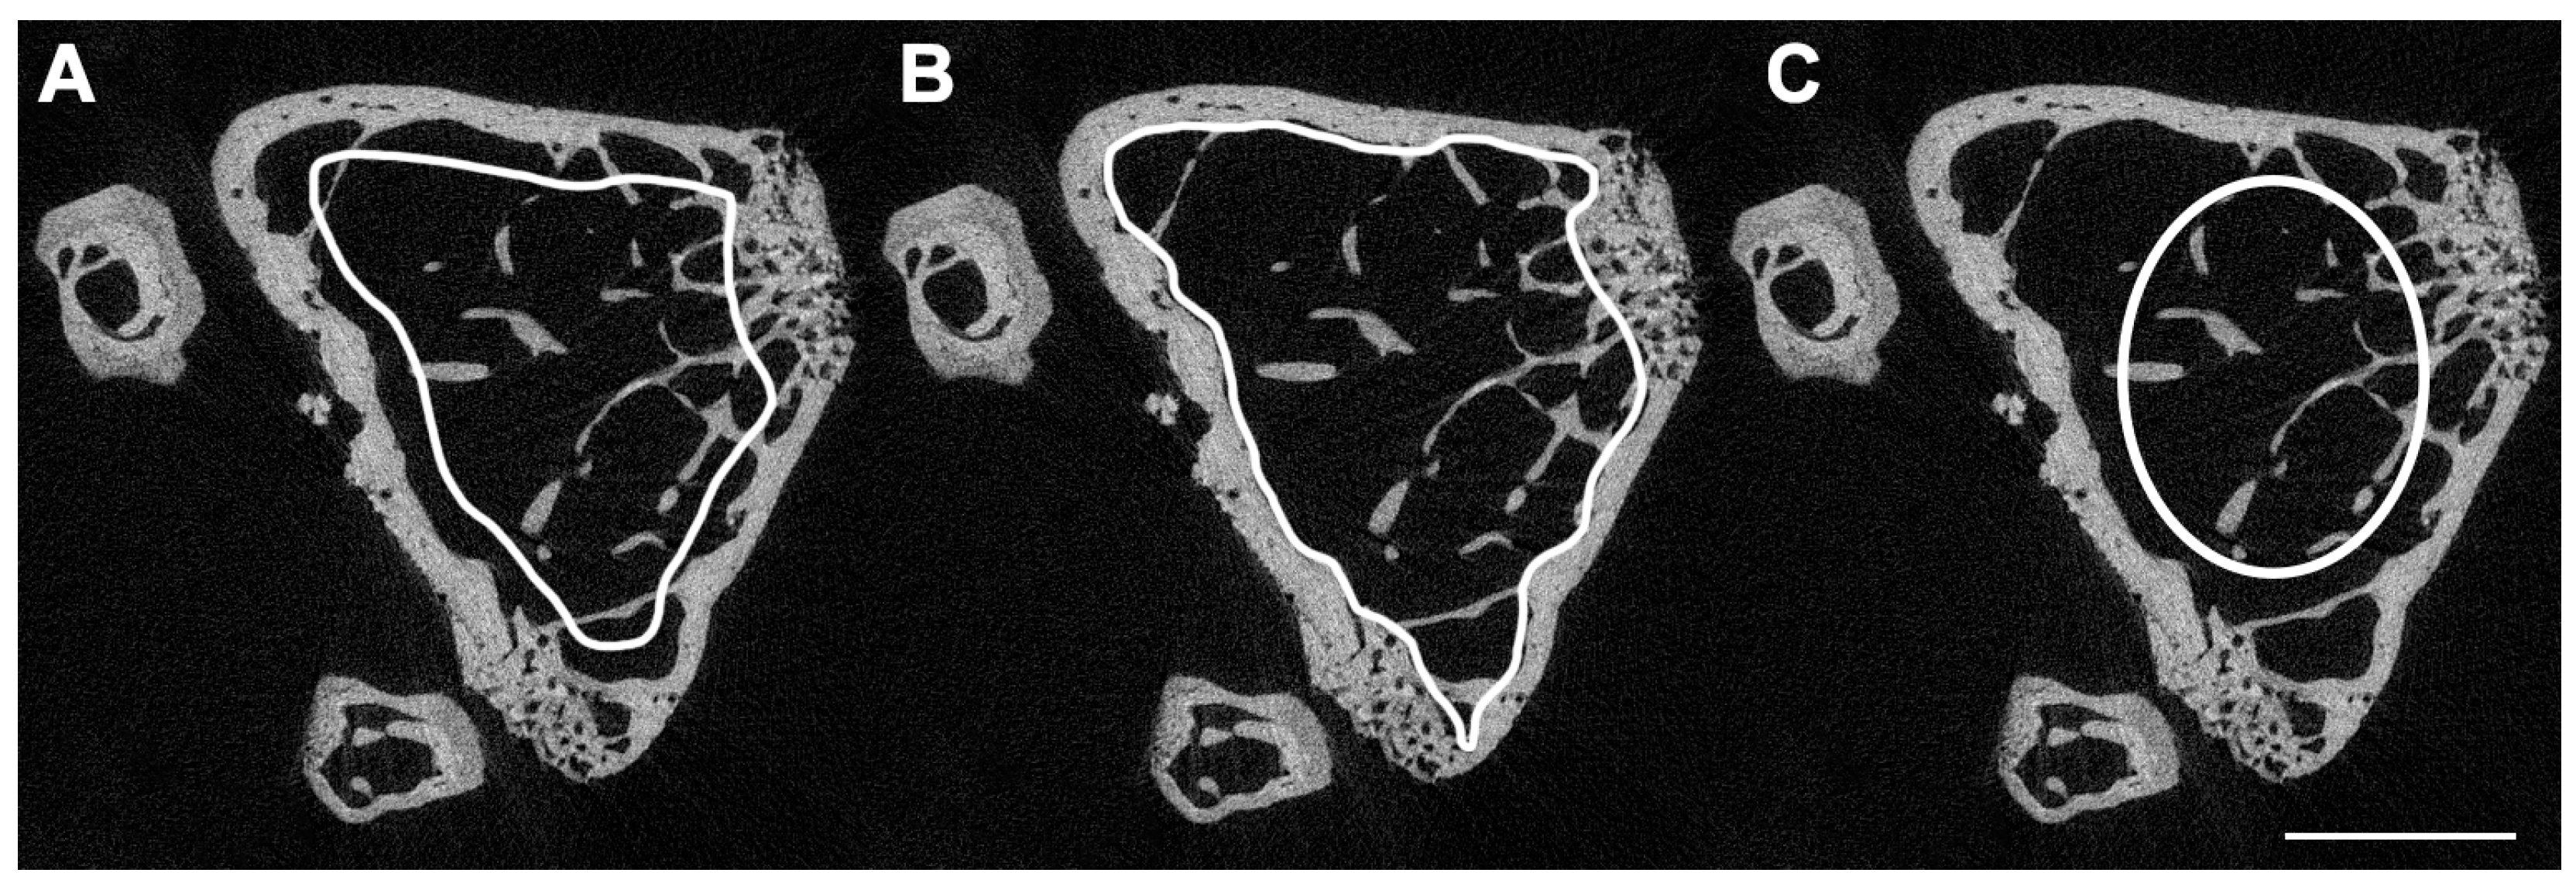

| Cortical morphology | ||

| Total cross-sectional area (Tt.Ar) | Total cross-sectional area inside the periosteal envelope. | mm2 |

| Cortical area (Ct.Ar) | Cortical bone area = cortical volume (Ct.V) ÷ (number of slices × slice thickness). | mm2 |

| Relative cortical bone area to tissue area (Ct.Ar/Tt.Ar) | Cortical area fraction. | % |

| Cortical thickness (Ct.Th) | Average cortical thickness. | mm |